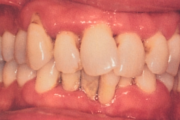

- igemed veritsevad (19)

- igemed punetavad (21)

- igemed on tursunud/vohavad (17)

- igemepiir on taandunud (3)

- igemepealne hambakivi (5)

- igemealune hambakivi (4)